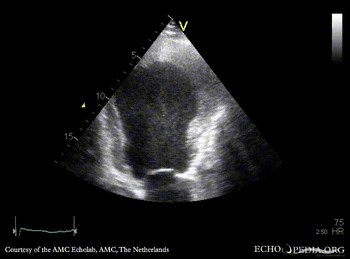

Thrombus in the apex of left ventricle

Courtesy of: AMC Echolab, AMC, The Netherlands

A3CH